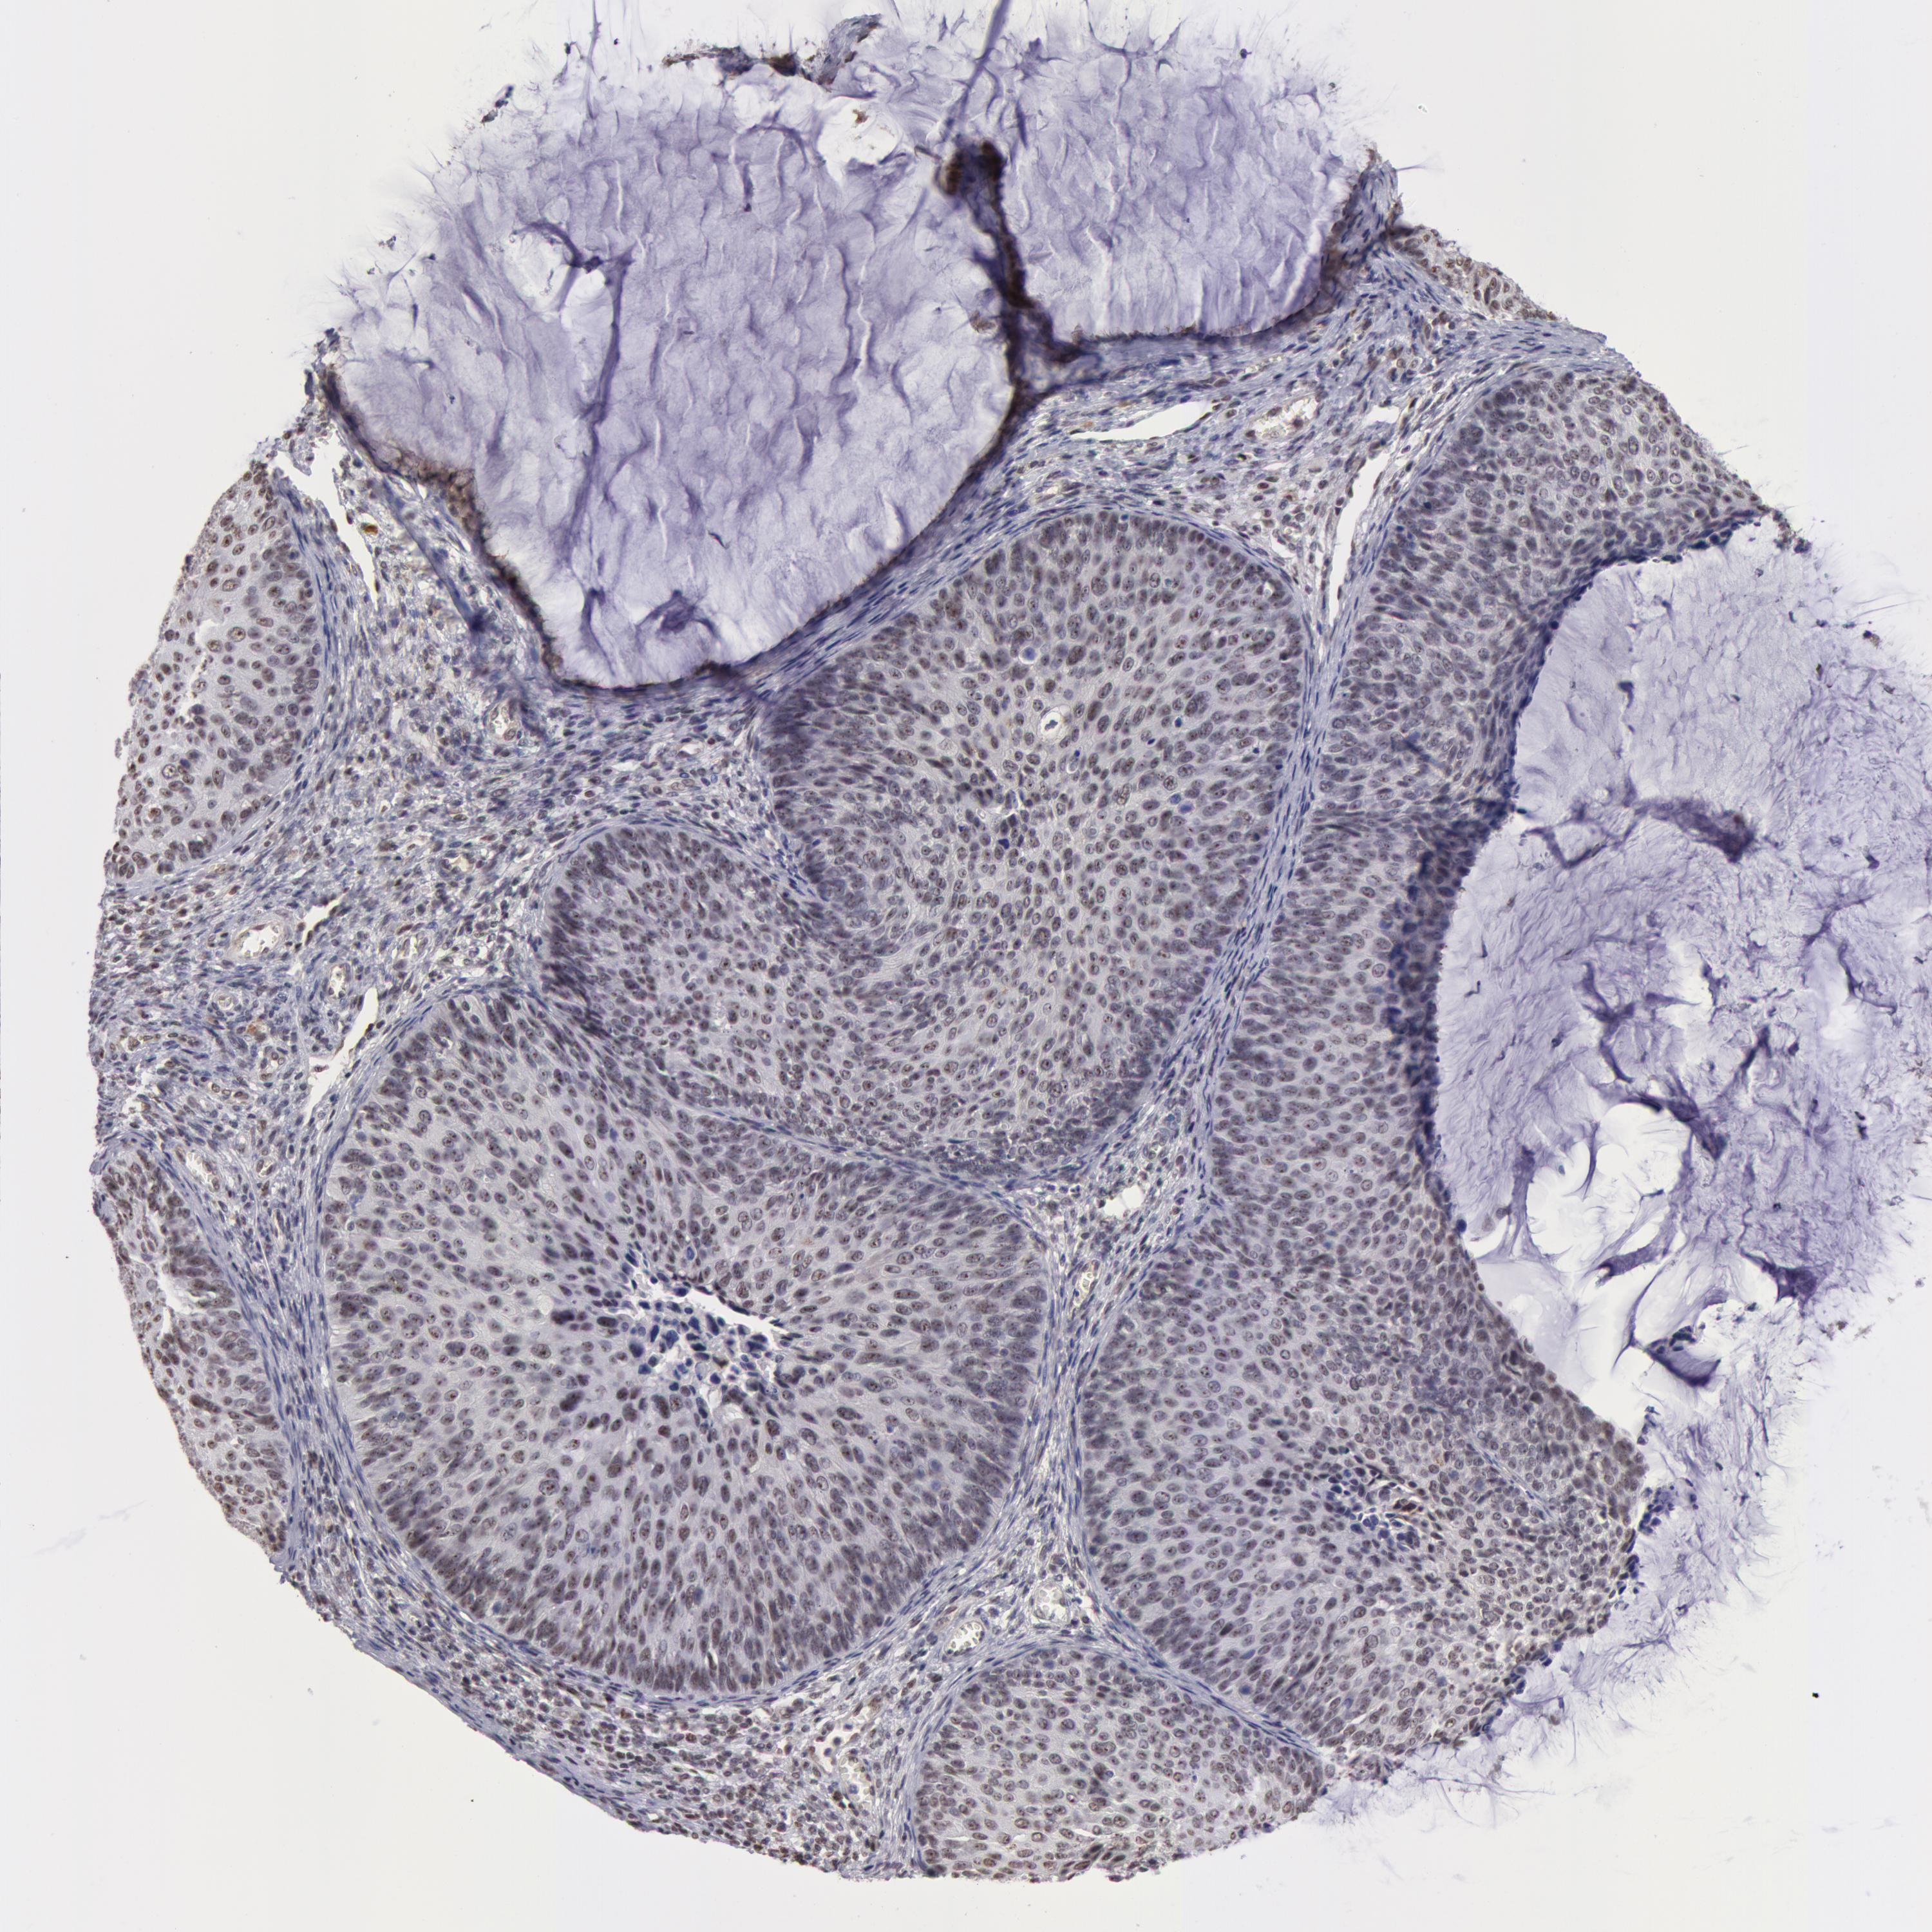

CERVICAL CANCER - Protein expressioni

A mouse-over function shows sample information and annotation data. Click on an image to view it in a full screen mode. Samples can be filtered based on level of antibody staining by selecting one or several of the following categories: high, medium, low and not detected. The assay and annotation is described here.

Note that samples used for immunohistochemistry by the Human Protein Atlas do not correspond to samples in the TCGA dataset.

Antibody stainingi

Antibody staining in the annotated cell types in the current human tissue is reported as not detected, low, medium, or high, based on conventional immunohistochemistry profiling in selected tissues. This score is based on the combination of the staining intensity and fraction of stained cells.

Each image is clickable and will lead to virtual microscopy that enables deeper exploration of all samples and also displays staining intensity scores, fraction scores and subcellular localization as well as patient and tissue information for each sample.

Antibody HPA001460

Staining

High

Medium

Low

Not detected

Intensity

Strong

Moderate

Weak

Negative

Quantity

>75%

75%-25%

<25%

None

Location

Nuclear

Cytoplasmic/membranous

Cytoplasmic/membranous,nuclear

Adenocarcinoma, NOS

Squamous cell carcinoma, NOS